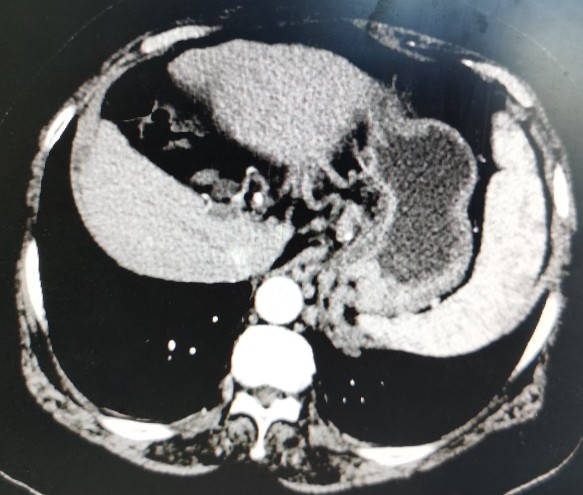

肝癌向下生长

栓塞后的影像图